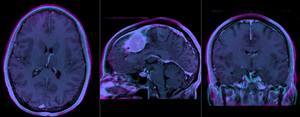

Slicer Registration Library Case #1: Follow-up MRI of Brain Tumor

Input

this is the fixed baseline image.

this is the follow-up scan, to be registered the baseline on the left

fixed image moving image

This case contains a baseline-followup pair of brain MRI. Goal is to align the follow-up image with the reference/baseline scan to assess changes, particularly in the tumor region.